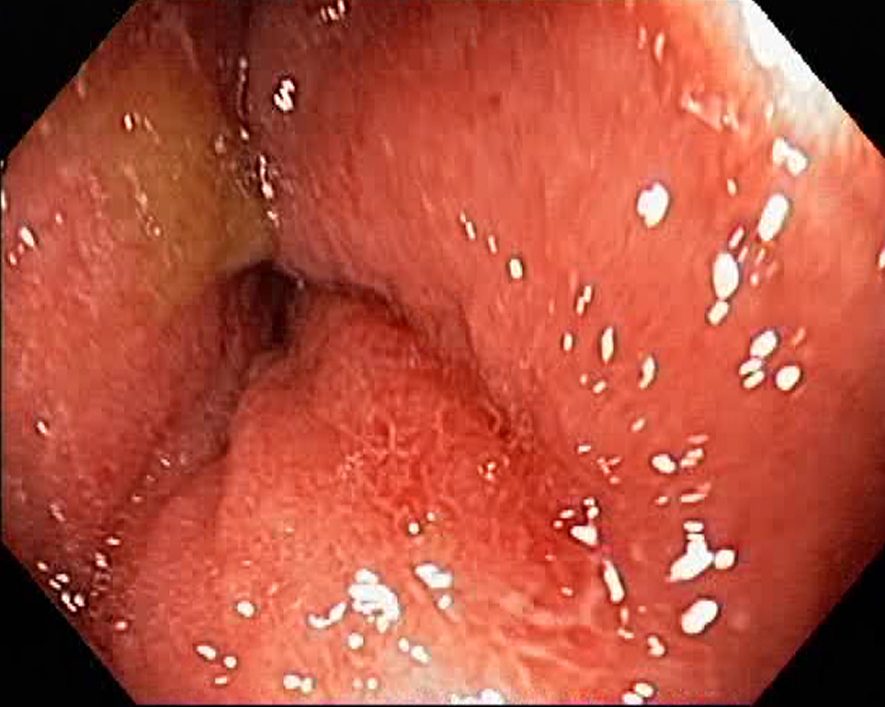

Campylobacter-Colitis